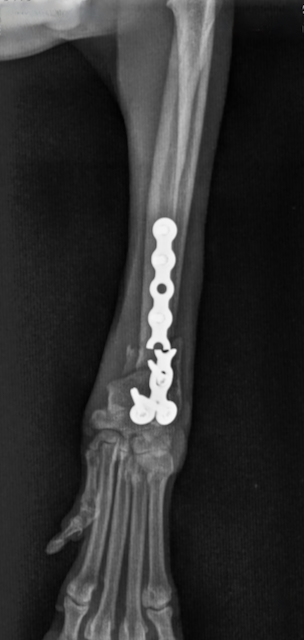

Re-Operation nach Plattenausriss

Seinen Übermut musste Kater Benny (Name geändert) neulich bitter bezahlen. Nachdem der zehn Jahre alte…